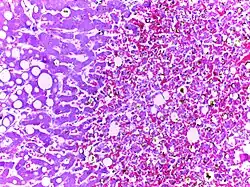

Fat necrosis | Breast lump showing an area of fat necrosis showing shadowy outlines of necrotic adipocytes surrounded by an inflammatory reaction with cholesterol clefts. | Category: Histopathology of liponecrosis | Liponecrosis |

Fatty change in liver | Hepatic parenchymal cell cytoplasm containing clear vacuoles containing fat of varying sizes, displacing the nucleus towards the periphery. | Category: Lipid steatosis | steatosis |

Fatty liver | Hepatic parenchymal cell cytoplasm containing clear vacuoles containing fat of varying sizes, displacing the nucleus towards the periphery. | Category: Lipid steatosis | steatosis |